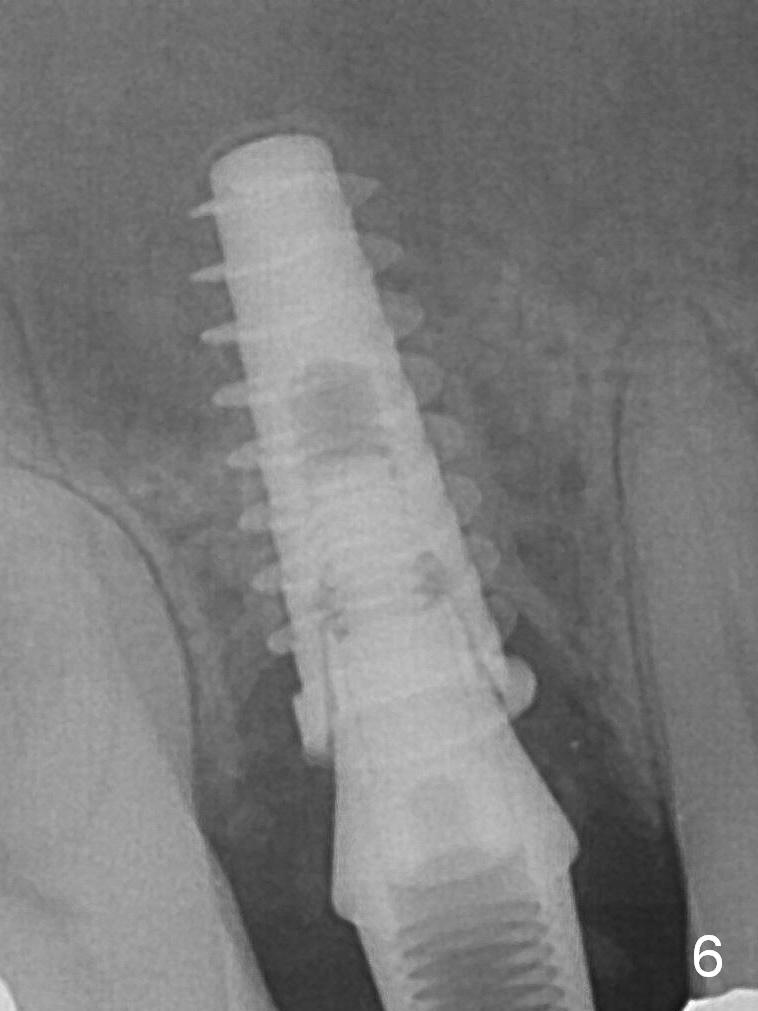

To prevent sinus lift related sinusitis, a shorter implant is going to be placed (Fig.1), approxi-mately 2 mm beyond the apex. Following extraction, the buccal plate (Fig.3a (coronal section): B) is not only ~ 2 mm shorter than the palatal one (P), but also thinner. Since the bone density of the palatal plate is higher, without osteotomy an implant is less likely placed in the middle of the socket (S (Fig.1); Fig.3b) than buccal (Fig.3c). Therefore drills are used to form osteotomy in the apical 1/3 of the palatal slope (Fig.3d (red arrow); SM: sinus membrane). When 3.3 mm Magic Drill (MD) is in place (Fig.2), the distal surface of the sinus septum is perforated without air leakage. Demineralized allograft (.0125-.085) is placed for sinus lift (Fig.4 *) prior to placement of 4.5x11 mm implant with ~ 30 Ncm. The implant is slightly buccal to the ideal position indicated in Fig.3e (curved blue line: sinus lift). A 4.5x4(2) mm pair abutment is placed for an immediate provisional to hold mineralized allograft in the remaining socket gaps (Fig.4 arrowheads, .5-1.5 mm). A 9 mm implant may avoid sinus floor perforation on the distal slope of the 2nd premolar. The osteotomy should have been established initially as mesial as possible. In fact the patient has nasal hemorrhage while sneezing for the first 2 days postop. Although he complains of pain buccal to the implant, the gingiva appears to heal 7 days postop (Fig.5). The distobuccal papilla appears to be displaced somewhat. Raising mucoperiosteal flap is most likely associated with postop pain and esthetic compromise. The implant appears to have osteointegrated 5 months postop (Fig.6). A 4.5 mmx15° 3 mm cuff angled abutment is placed for final restoration. The distolingual portion of the implant is supported by the regenerated bone 3 years post cementation (Fig.7,8).